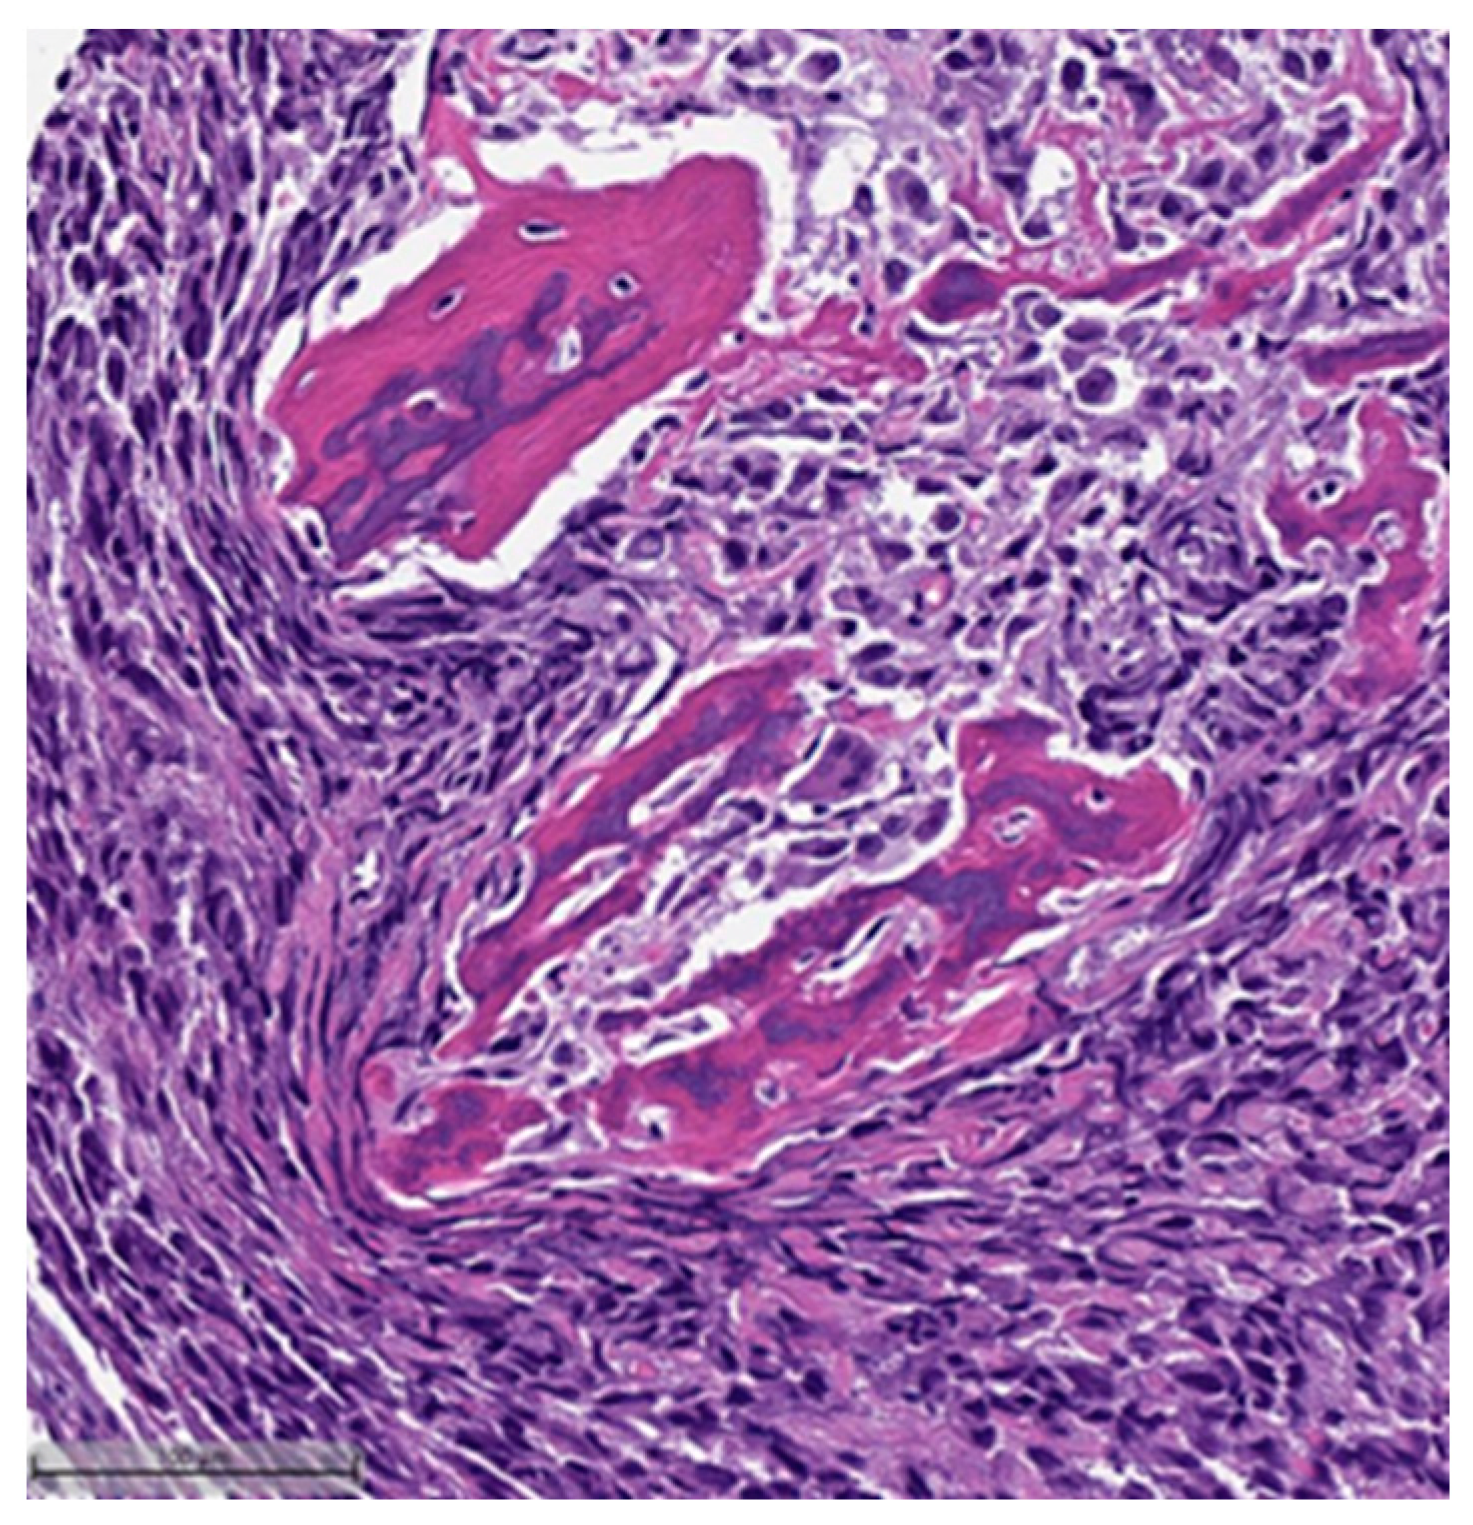

Figure 2. Squamous cell carcinoma component (H&E, 20×).- Spindle cell carcinoma (SpCC) (Figure 3);

Figure 3. Spindle cell carcinoma (H&E, 20×). - Metaplastic carcinoma with heterologous mesenchymal differentiation (MCHMD);

This system is primarily based on the specific metaplastic elements present within the tumors, while also highlighting the potential overlap that can exist between various histological subtypes [6]. Consequently, numerous cases diagnosed as MpBCs, are accompanied by a detailed description of the histological component or a combination of different component types and/or differentiations. The following figures illustrates a few examples: spindle cell carcinoma component with pleomorphic features (Figure 4), metaplastic breast carcinoma with chondroid differentiation (Figure 5), metaplastic breast carcinoma with a matrix-producing component (Figure 6), metaplastic breast carcinoma with osseous differentiation (Figure 7), and extensive trabeculae bone and hematopoietic tissue (Figure 8).

Figure 4.

Spindle cell carcinoma component with pleomorphic features (H&E, 20×).